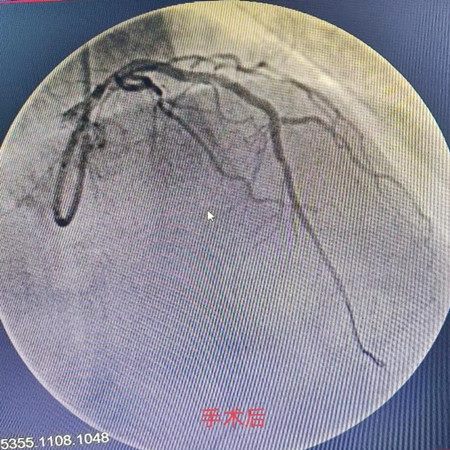

经与家属协商并签字后决定对左前降支中段闭塞处行急诊PCI术植入支架2枚,前降支远段血流恢复TIMI3级。

术后患者胸闷症状明显缓解。家属对梁海军主任、黄斌副主任及潢川二院心内科团队联手成功挽救患者生命表达了衷心地感谢。